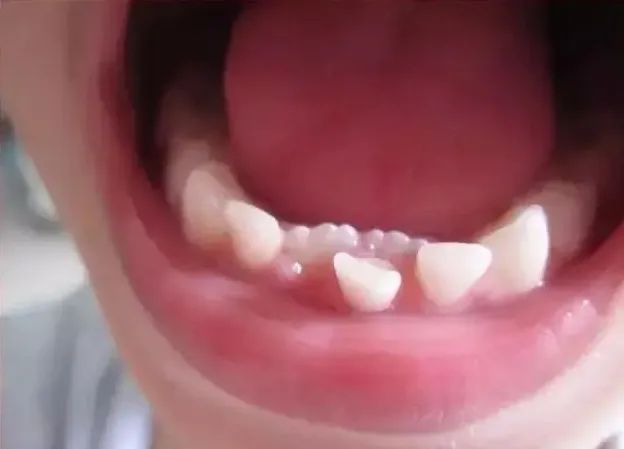

6. 出现“双层牙”怎么办?

门牙一般从乳牙内长出,如果孩子的乳牙还没脱落,旁边又长出新牙时,就会出现双层牙。

“双层牙”危害不小,不但会影响牙齿的美观,还会使恒牙排列错位,影响牙齿的咀嚼功能。

所以如果孩子出现“双排牙”,要及早去医院拔掉乳牙,为恒牙长出让出位置。